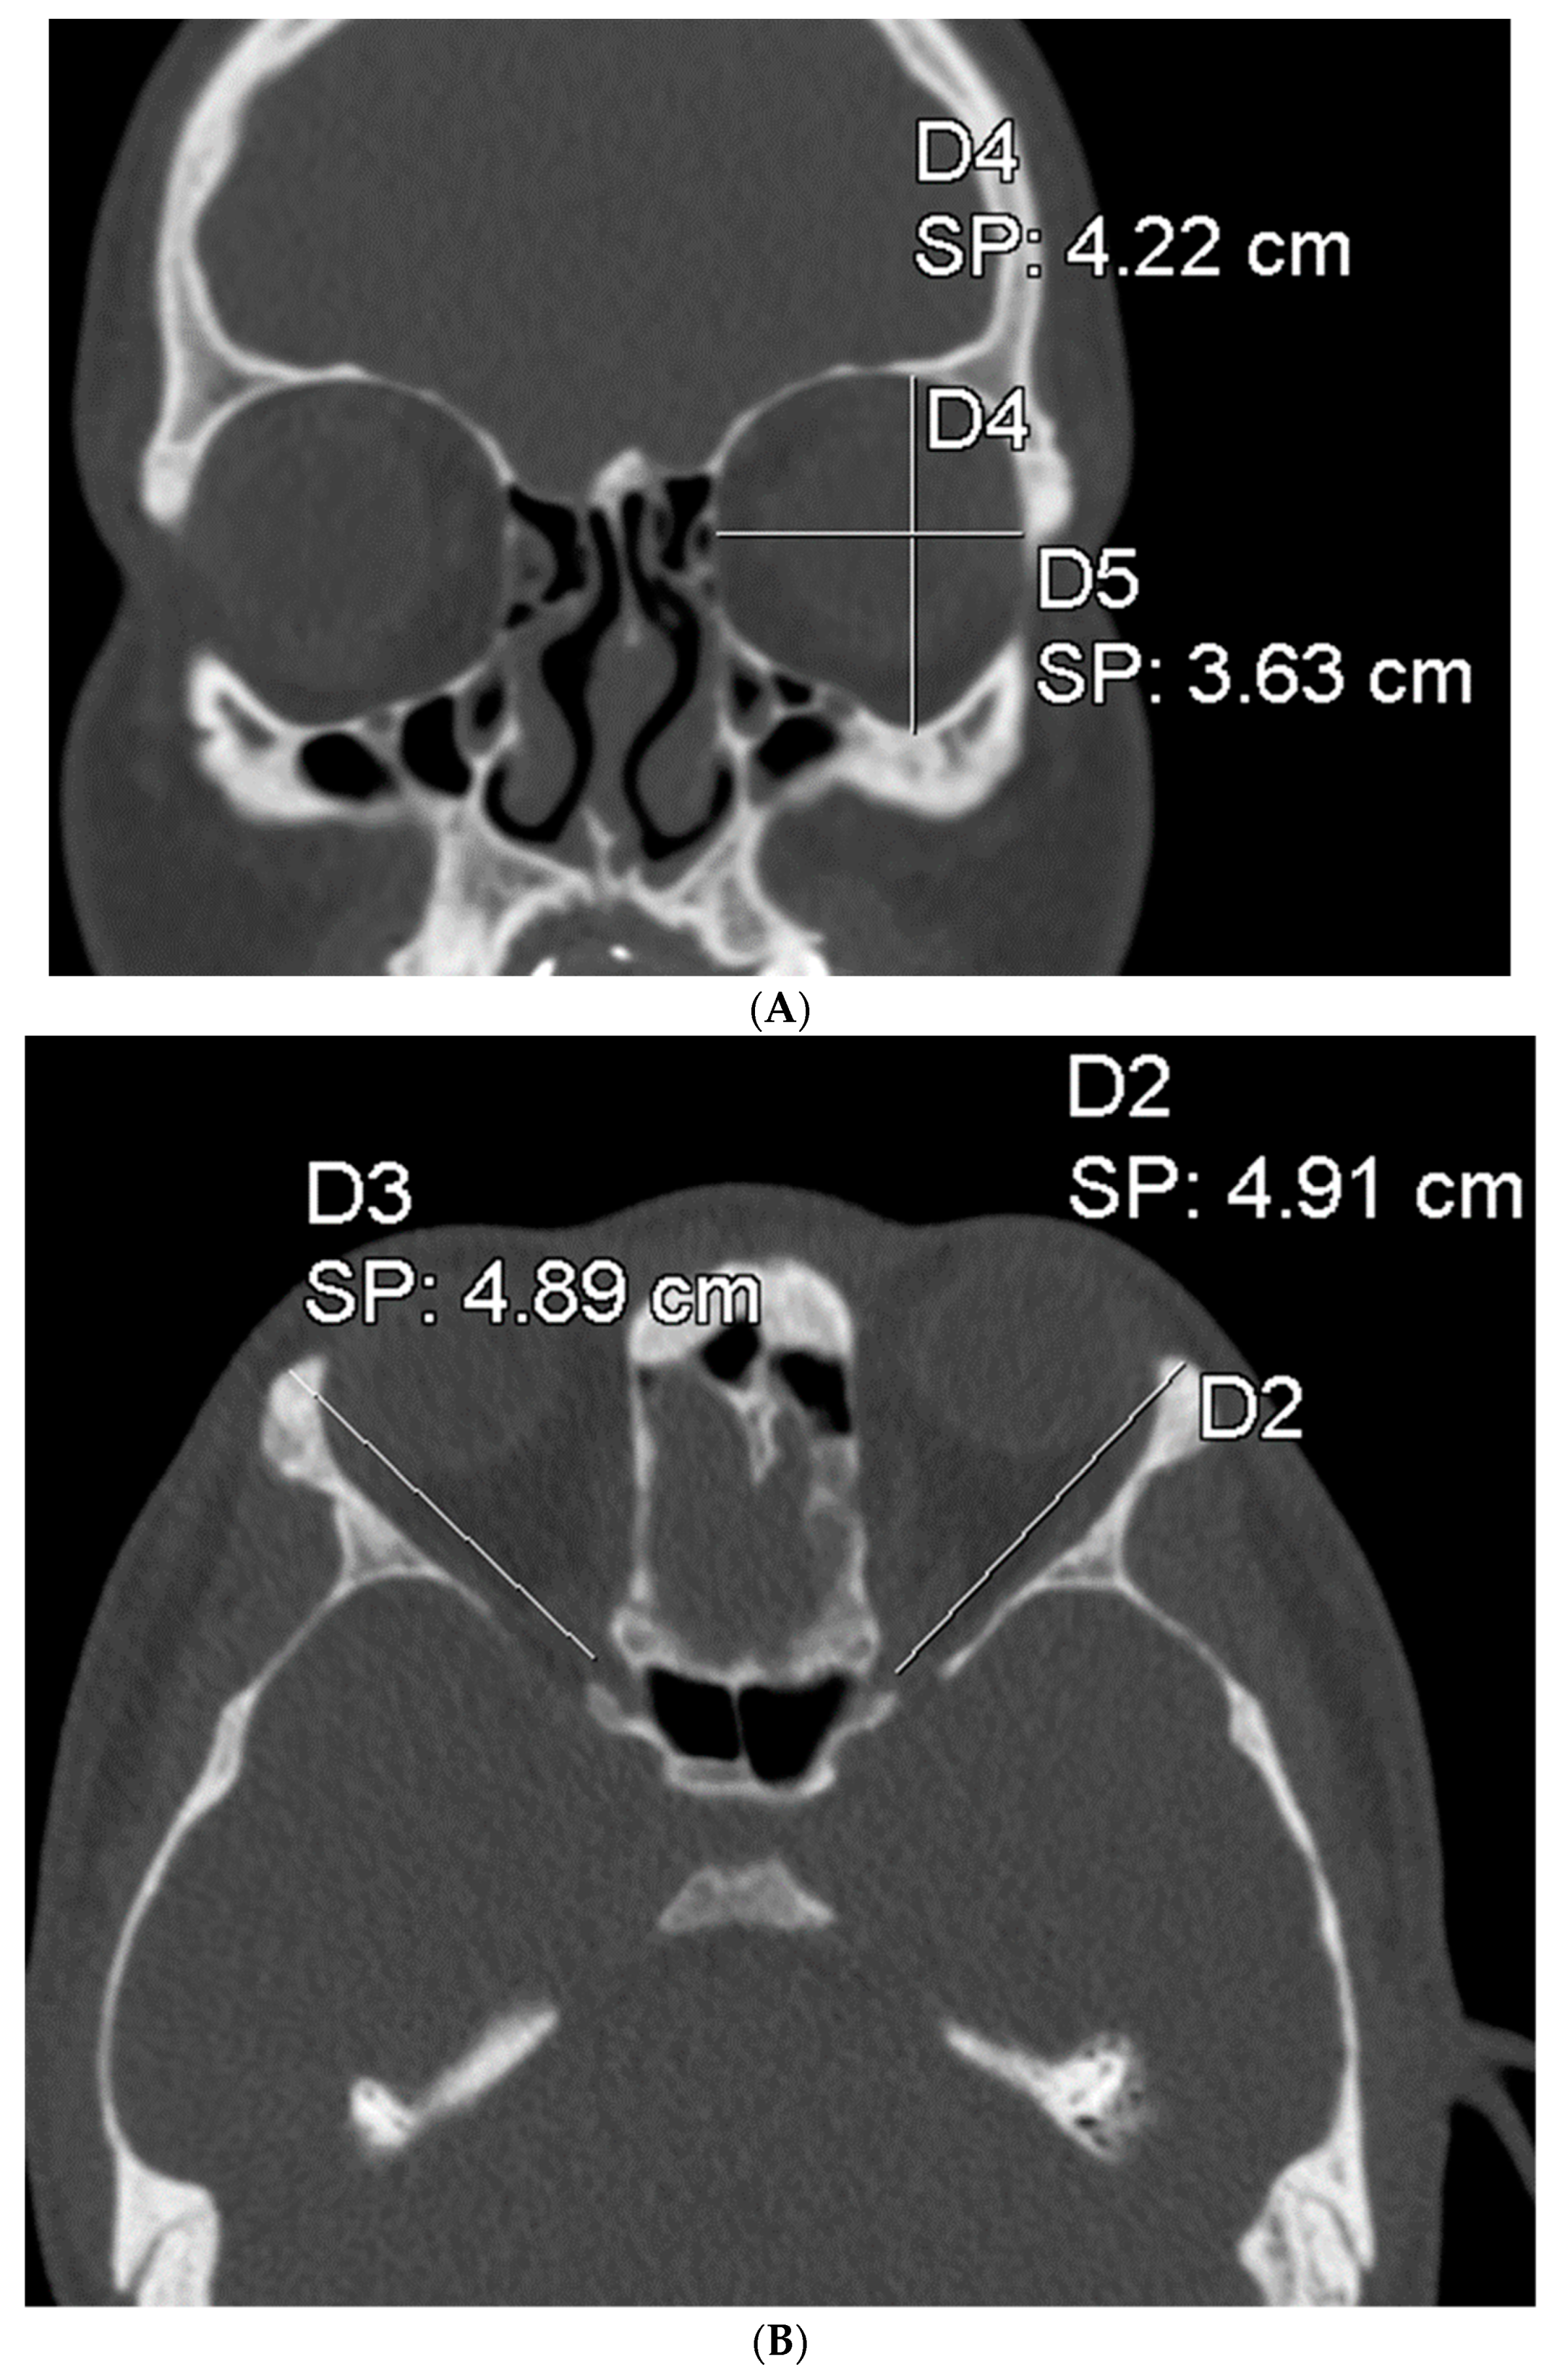

To assess the size of the rim of bony orbit, the width and height were measured from the most anterior CBCT or CT slice showing the whole orbital rim (Figure 2A), and the depth was the distance from the frontozygomatic suture to the optic canal (Figure 2B). The position of bony orbit was assessed as the distance of the cranio-lateral border of the infraorbital canal opening to the inner postero-caudal wall of the sella turcica, measured from an oblique sagittal plane (Figure 2C). Helsinki University Hospital radiologist workstations and Syngo software (Siemens Healthineers, Erlangen Germany) were used for the analysis according to the manufacturer’s instructions for quantitative analysis. The volume of bony orbit was measured with semi-automated segmentation to avoid potential measurement-related bias since the cleft side is always visible to the radiologist in the lower sections during the orbital analysis. Semi-automated orbital volume analysis was performed using CMF Orbital Software (Disior Ltd., Helsinki, Finland). To use the software, the radiologist only selects a seed point inside the orbital vault and confirms the side to be examined. The apex of the orbit at the conjunction of the optic nerve and bulbus was used as a seed point in all cases. After selecting the seed point, the virtual program-generated triangle mesh iteratively expands from the starting position until it meets the bony walls of the orbit. The anterior expansion of the volume mesh network automatically stops when the mesh reaches the bony rim of the orbit (Figure 3). This system is described in more detail, and the reliability of the software measurements is proven to be high (0.992 (95% CI 0.987–0.997 intraobserver ICC and 0.989 (95% CI 0.983–0.993)) interobserver ICC in intact orbit) [25]. All volume analyses and the surface reliability of the software algorithm were confirmed by the radiologist in all cases. All the measures of the cleft patients were made by the same radiologist (E.P.).

Figure 2.

(A) The width and height of the bony orbit from the most anterior CBCT or CT slice showing the whole orbital rim. (B) The depth from the frontozygomatic suture to the optic canal opening. (C) The position of bony orbit was assessed as the distance of the cranio-lateral border of the infraorbital canal opening to the inner posterocaudal wall of sella turcica, measured from an oblique sagittal plane.